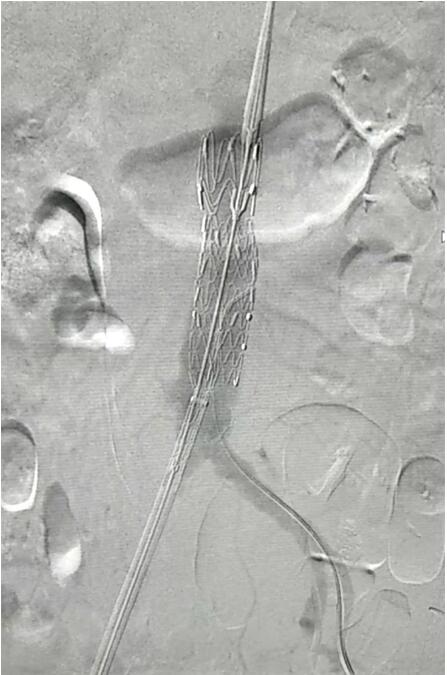

患者因腹部搏動(dòng)性腫塊行成已有4年,伴右下腹疼痛6小時(shí)入院,既往有高血壓病史,患者入院后血壓177/96mmHg,醫(yī)護(hù)人員隨即予以控制血壓、止痛處理,CTA檢查提示患者有腎下腹主動(dòng)脈瘤,合并心 、肝 、肺 、腎等重要臟器疾患,根據(jù) Laplace定律,動(dòng)脈瘤直徑越大壓力越大,老人動(dòng)脈脆弱,動(dòng)脈瘤隨時(shí)有破裂的可能性,其危險(xiǎn)性大。血管介入科排除各種困難,在麻醉科協(xié)作下行腹主動(dòng)脈瘤覆膜支架隔絕術(shù)(“褲衩”支架植入),手術(shù)持續(xù)了1個(gè)半小時(shí),患者術(shù)后安返病房,麻醉醒后露出了微笑,向醫(yī)務(wù)人員伸出大拇指。

血管介入科行腹主動(dòng)脈瘤覆膜支架隔絕術(shù)(“褲衩”支架植入)。圖1